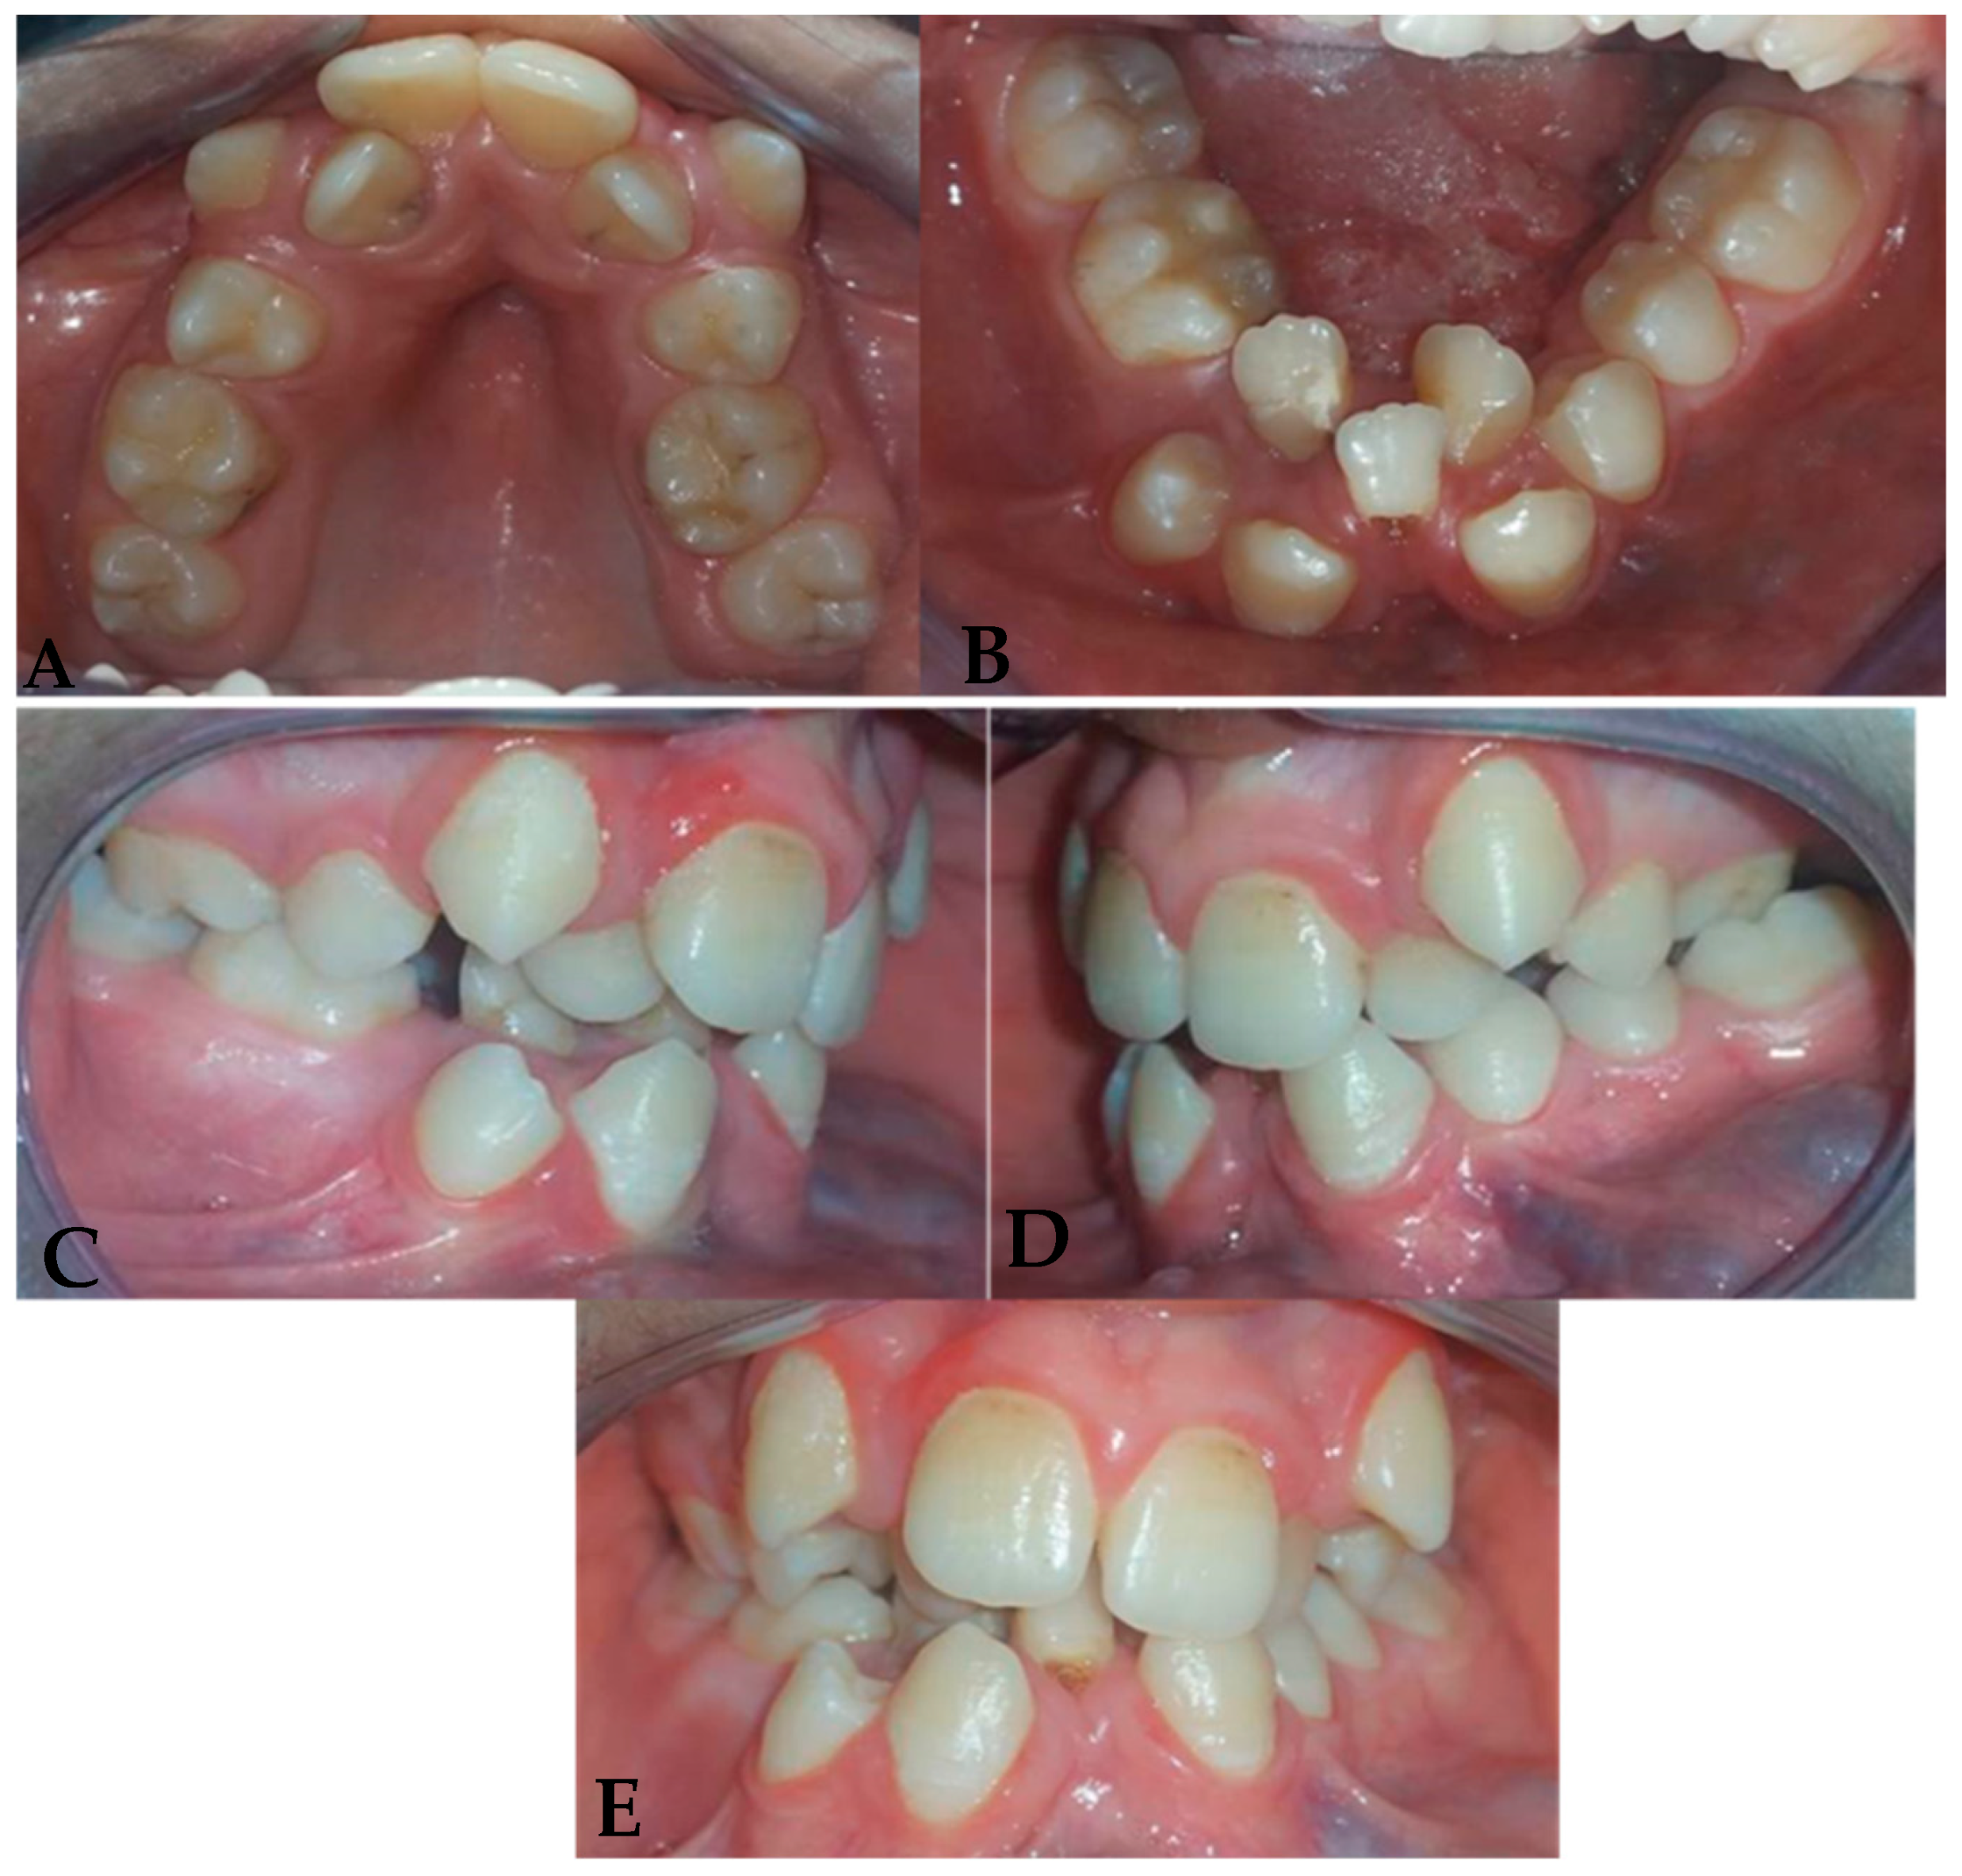

2.4. Intraoral Clinical Examination (Figure 2)

- Maxillary arch: Crowding of the anterior teeth and a distinctive V-shaped arch are associated with the absence of teeth 14 and 24. Notably, the buccal positions of teeth 13 and 23 and the lingual positions of teeth 12 and 22 demonstrate difficulty in finding space and maintaining good symmetry.

- Mandibular arch: Similar crowding and a V-shape in the mandibular arch are accompanied by the absence of teeth 31, 36, and 45, as well as poor positioning of the incisors, reinforcing the skeletal adaptations caused by the lack of lingual function.

- Interarch relationships: Class III canine and molar relationships characterize a reverse overjet between teeth 26 and 36, with both maxillary and mandibular arches showing endognathia, a hallmark of altered growth patterns.